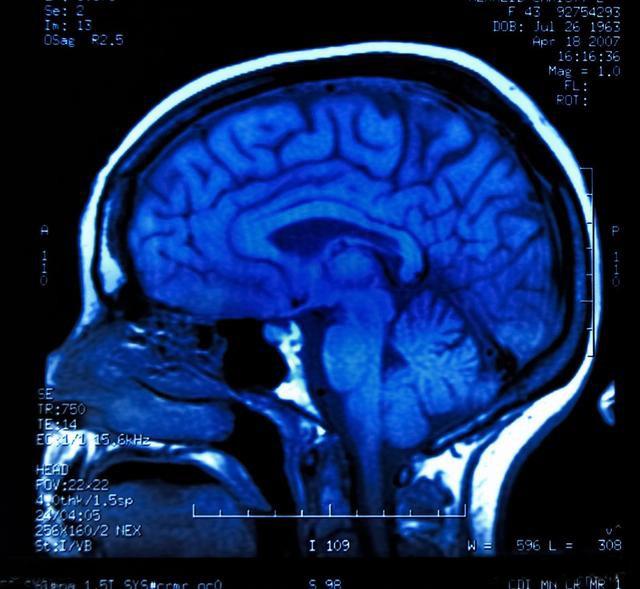

头颅磁共振

有人为查肺癌为什么要查头颅磁共振,这主要是看一下肺癌有没有转移到头部,因为一旦肺癌转移到大脑,会对患者的生存时间带来重要影响,需要针对脑局部的肿瘤病灶做单独的诊治。